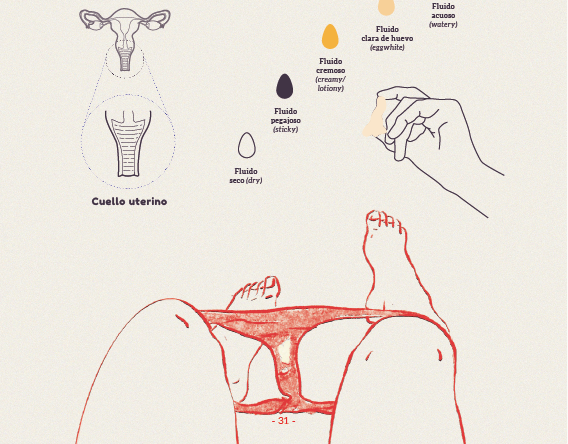

Librillo: Consciencia de la fertilidad